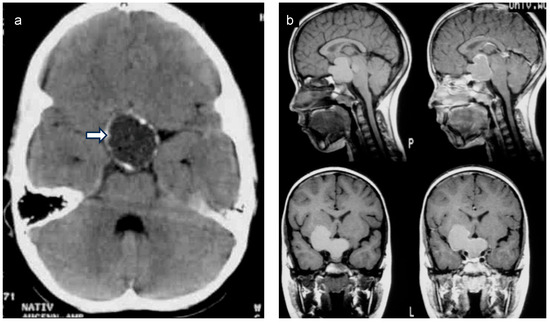

Children diagnosed with CP have a median age of 5 to 12 years old and present with varied initial symptoms and complaints. Headache, stunted growth, polyuria/polydipsia, and visual impairment can be the first signs of a CP during childhood and adolescence [9,10]. When CP is suspected, patients should ideally undergo comprehensive whole-brain magnetic resonance imaging (MRI), assessing the sellar and suprasellar area (Figure 3) via 3D high-resolution coronal, axial, and sagittal T2-weighted images and volumetric T1-weighted sequences. For initial MRI scans of CPs, using an intravenous contrast agent is recommended. To guide diagnosis, MRI should be supplemented with computed tomography (CT) scans (limited sellar scans sparing the lenses, without an intravenous contrast agent) to visualize calcifications. After neurosurgical intervention, an MRI scan within 4 weeks serves as the initial postoperative imaging method for assessing the degree of surgical resection [11]. Typically, CP is located at a single central nervous system location, being unifocal and often having solid and cystic tumor components [12]. Rare cases of ectopic CP have been reported [13].

Figure 3.

(a) Native coronal computed tomography (CT) of the skull of a patient with childhood-onset craniopharyngioma, depicting calcifications in the cyst membrane of a craniopharyngioma (arrow). (b) Sagittal and frontal magnetic resonance imaging (MRI) of a patient with childhood-onset craniopharyngioma. Both patients were recruited in the KRANIOPHARYNGEOM 2007 trial.